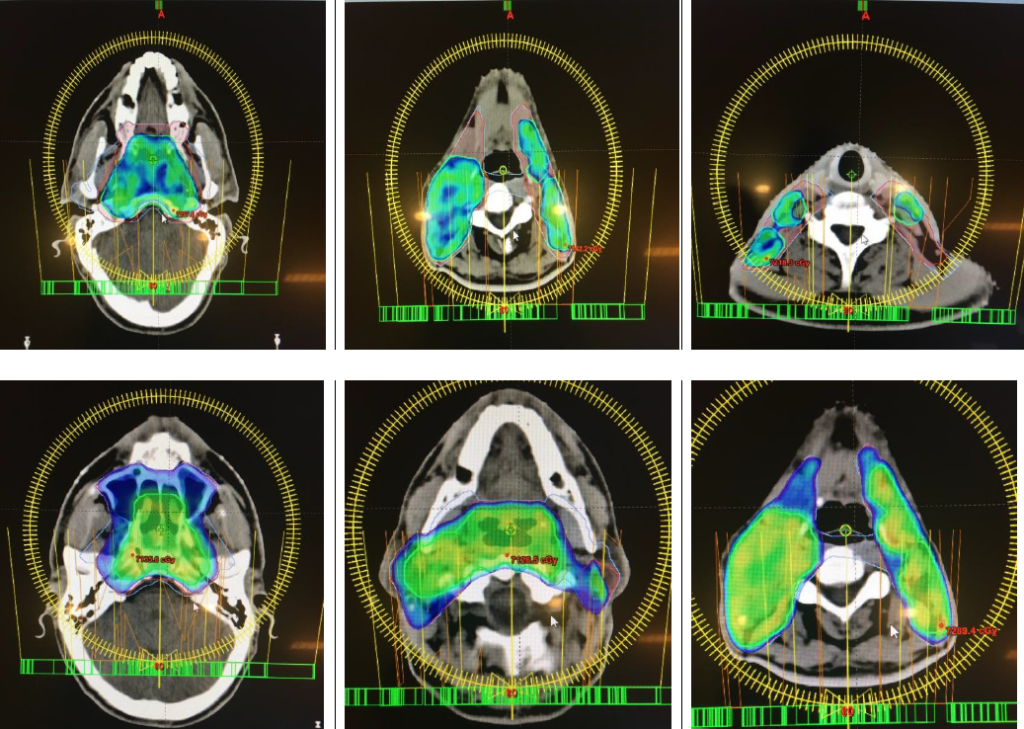

Friedemann Herberth

Score: 99.3/ 100

Hospital: Kantonsspital St.Gallen

Technique: VMAT

Rank: Second Top (Eclipse)

Job Title: Medical Engineer